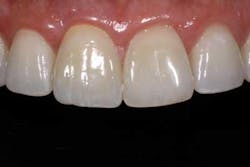

Of all the problems that can occur with implant placement in the anterior, not controlling the zenith of gingival contour may be the most troublesome when it comes to anterior esthetics. Gingival zenith or height of gingival contour is defined as the apex of the gingival height. There are many ways to lose several millimeters of peri-implant mucosa, and it has been shown that even a 1 mm apical displacement of peri-implant mucosa may result in insurmountable limitations in anterior implant esthetics. Things such as deep implant placement, buccal resorption, and relative tooth eruption are just some of the things that can cause this loss of tissue.

When planning surgery with my periodontist, we both decide where we want the zenith to be esthetically, and then plan implant placement 3 mm apical and 2 mm palatal to this location. Biologically speaking, this location will allow us to preserve the zenith from a placement standpoint. Keep in mind that we need to have the tissue healthy and under control prior to starting any procedure.

Now comes the tricky part — the provisional. Prosthetic control of peri-implant tissue is achieved by properly utilizing your abutment and provisional form. When placing the provisional, it is important to maintain gingival zenith. When fabricating a provisional, my rule of thumb is to create a flat or slightly convex surface facially and lingually, and a concave surface interproximally. This will minimize impingement on the tissue interproximally and, if anything, allow for “overgrown tissue” to develop. This tissue can be easily contoured prior to final placement to give an ideal esthetic gingival architecture.